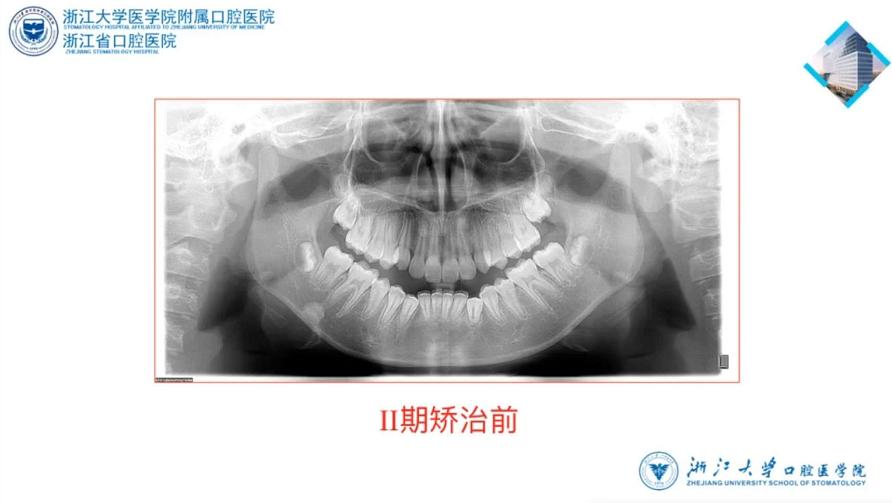

诊断:

1、安氏二类1分类错

2、凸面型,下颌后缩

3、前牙三度深覆、三度深覆盖

4、上下牙列中度拥挤

5、咬下唇习惯、口呼吸习惯